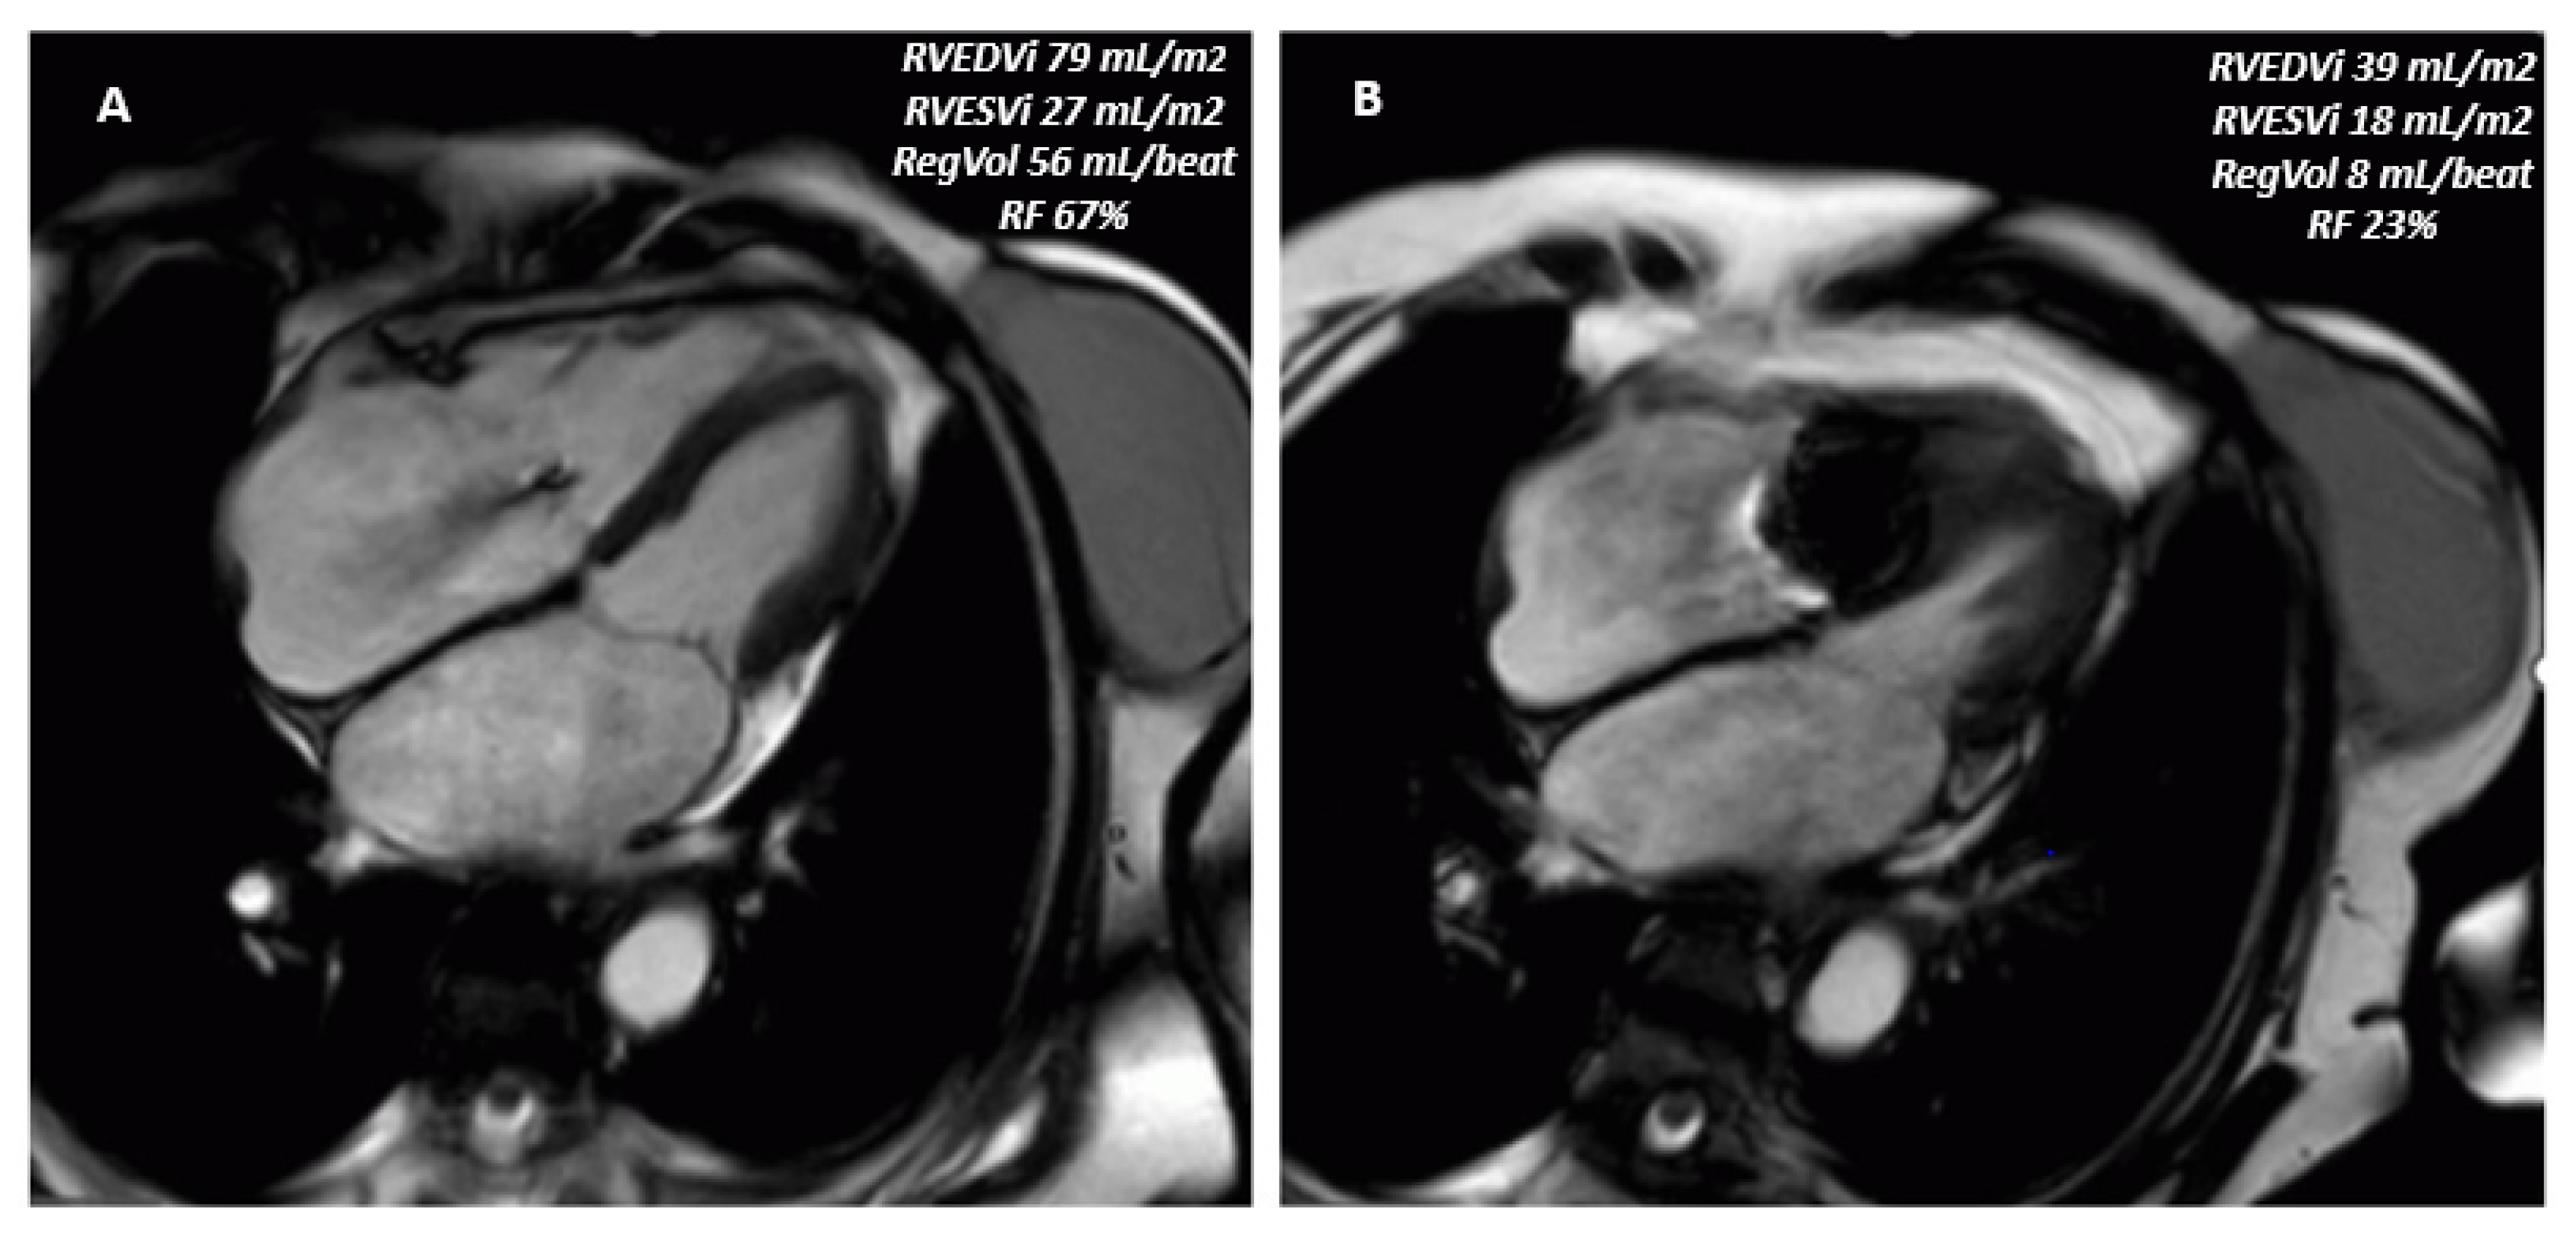

- Doldi, P.M.; Weckbach, L.T.; Fink, N.; Stolz, L.; Ennin, C.; Dinkel, J.; Lurz, P.; Thiele, H.; Hahn, R.T.; Cavalcante, J.L.; et al. 3D Echocardiographic and CMR Imaging for the Assessment of Right Ventricular Function and Tricuspid Regurgitation Severity. Circ Cardiovasc. Imaging 2025, 18, e017638. [Google Scholar] [CrossRef]

| Cardiac CMR | RVEF, RV volumes, fibrosis detection | Gold standard for RV volumes and function; not operator-dependent | Limited availability, contraindications (e.g., devices), expensive, does not consider the direction of the flow |